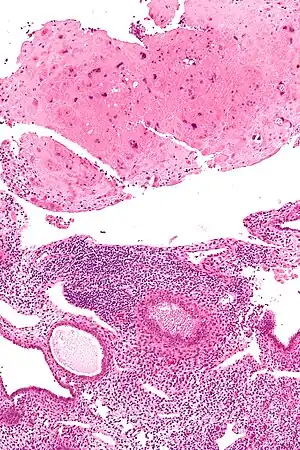

| Micrograph of a placental site nodule (top of image). H&E stain. | |

Typically, they consist of pink (hyaline) material using the standard stain and contain few cells. Bizarre multinucleated cells may be present; however, there is no mitotic activity. The differential diagnosis includes (cervical) squamous cell carcinoma, gestational trophoblastic disease, and exaggerated placental site.